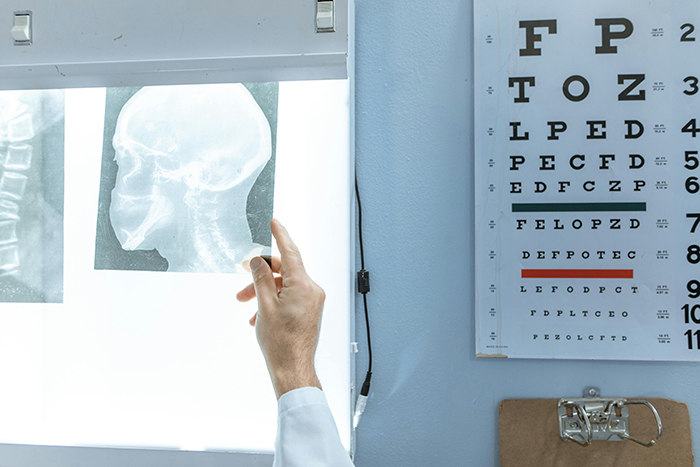

En ese contexto, Siemens Healthineers llega con desarrollos que recorren toda la ruta del diagnóstico. La nueva resonancia MAGNETOM Free.XL, con un túnel de 100cms de ancho, que abre posibilidades reales para pacientes que antes no podían realizarse un examen por claustrofobia, movilidad reducida u obesidad, al tiempo que habilita procedimientos intervencionistas guiados por RM (Resonancia Magnética) con mayor comodidad y precisión. En ultrasonido, la expansión de UDFF (Ultrasound Derived Fat Fraction) permite detectar y cuantificar enfermedad hepática metabólica con una accesibilidad inédita, llevando capacidades antes reservadas a centros de alta complejidad directamente a la atención primaria. La tomografía de conteo de fotones, apoyada en herramientas impulsadas por inteligencia artificial, ofrece un análisis de placa más preciso de la enfermedad coronaria para anticipar riesgos que pueden ser letales si no se detectan a tiempo. Y en entornos de radiología y cardiología intervencionista, se impulsa la terapia de precisión con un nuevo portafolio de imagenología avanzada que integra inteligencia artificial para optimizar la planificación y ejecución de procedimientos mínimamente invasivos. Estas soluciones ofrecen control inteligente de la dosis y reducción avanzada del ruido en tiempo real, generando imágenes de alta fidelidad que brindan a los equipos clínicos la confianza necesaria para intervenir con mayor seguridad y exactitud, incluso en los casos más complejos.